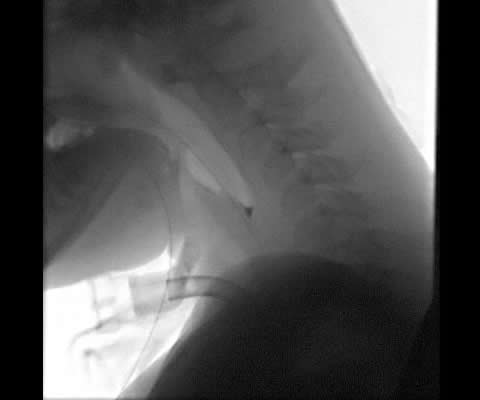

In paediatrics, instrumental assessment is usually performed using Videofluroscopy (VFS). Fig 1 shows different VFS views of a paediatric tracheostomy. Select the numbers to view each image or use the Previous and Next buttons.